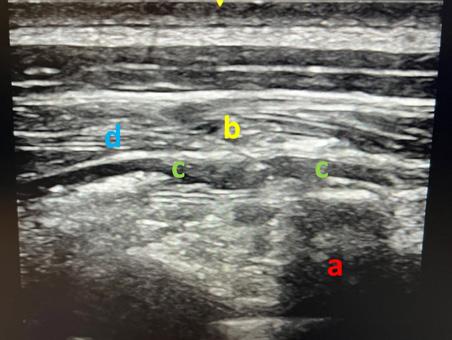

Table des illustrations

1. Korte, Wolfgang: Moderne Gerinnungsdiagnostik: wie hilft sie uns? http://www.anaesthesie-stgallen.ch/ Informationen_fuer_Fachpersonen/Fruehere_Veranstaltungen/IPS_Symposium_2008/05Korte.pdf

2. Görlinger K, Bergmann L & Dirkmann D. Coagulation management in patients undergoing mechanical circulatory support. Best Pract & Res Clin Anaesthesiol. 2012;26:179-198.

3. et 4. Gauger MS, Kaufmann P, Kamber F et al. Rotational Thromboelastometry Values After On-Pump Cardiac Surgery – A Retrospective Cohort Study. Semin Cardiothorac Vasc Anesth. 2022;26:209-220.

Laufbahnplanung auf

Die ideale Plattform für Berufs- und Bildungsprofile von Gesundheitsfachpersonen, weil

•alle Diplome und Zeugnisse an einem Ort zentral und elektronisch abgelegt sind

•ein stets aktueller Lebenslauf generiert werden kann